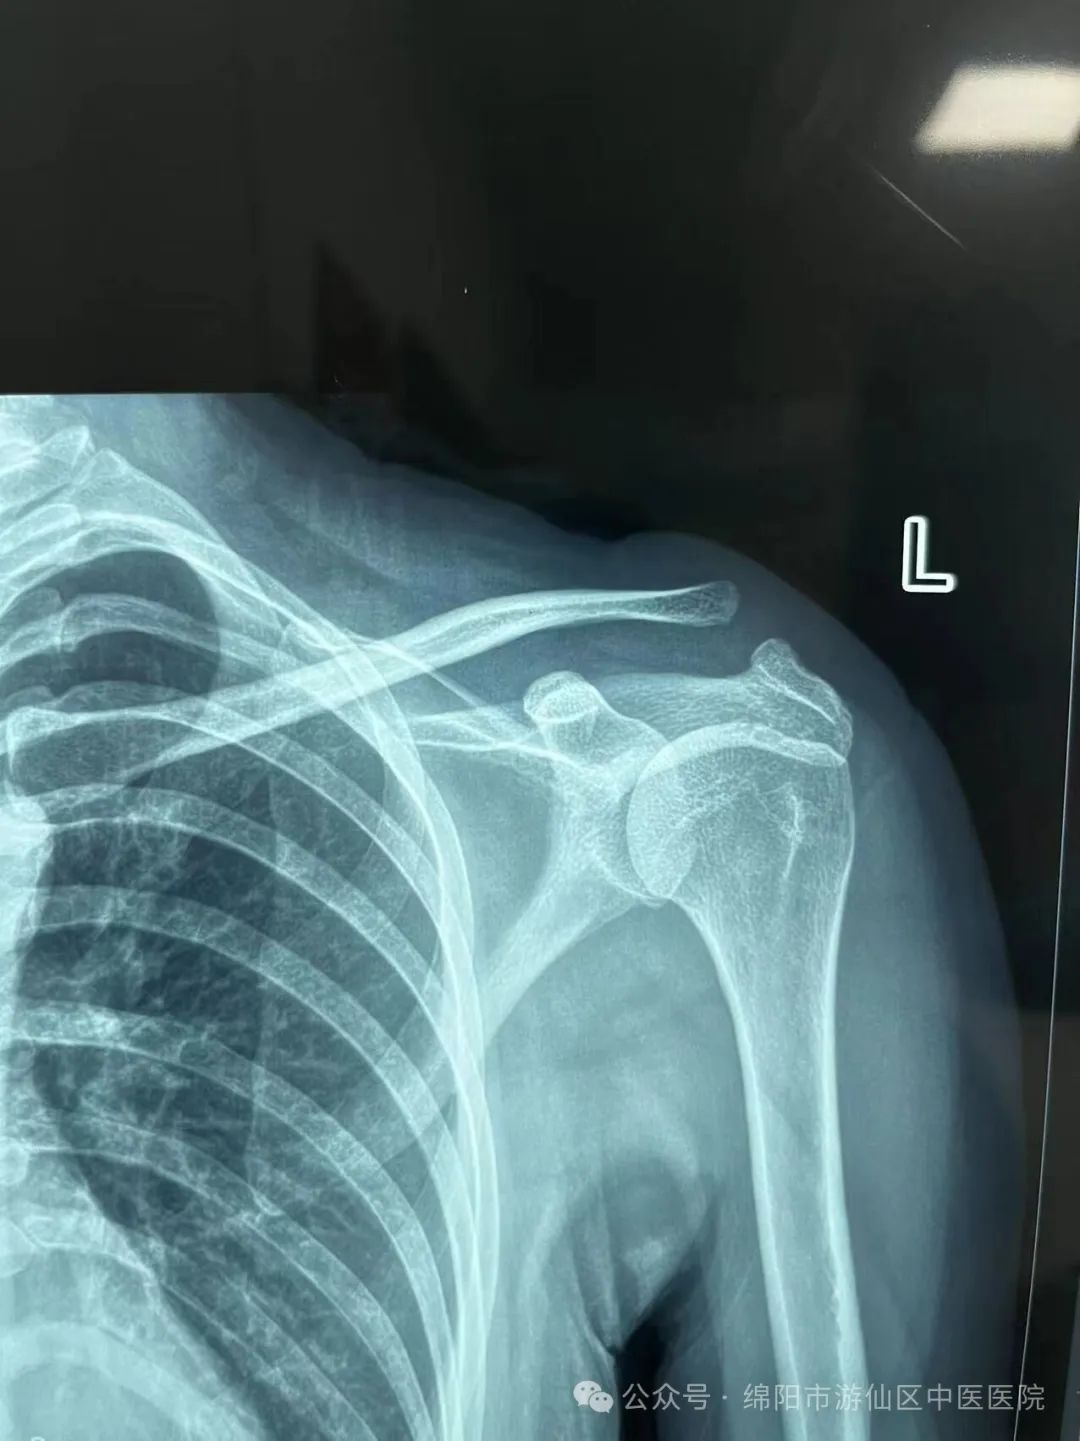

• 游仙分院:骨伤科(疼痛科):成功开展微创带袢钢板治疗肩锁关节脱位术

游仙分院:骨伤科(疼痛科):成功开展微创带袢钢板治疗肩锁关节脱位术 2024-02-09 作者:张春华